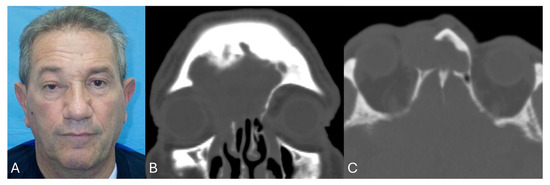

| 1 | M | 47 | Frontal-ethmoidal mucocele | Frontal wall erosion with skin fistulization | 28 min (about 5 h) | 50 months | No | Resolution of the symptom |

| 2 | M | 68 | Recurrent frontal sinusitis | Headache, Rhinorrhea | 26 min (about 5.5 h) | 46 months | No | Resolution of the symptom |

| 3 | M | 53 | Frontal-ethmoidal mucocele | Headache, pain | 25 min (about 4 h) | 43 months | No | Resolution of the symptom |

| 4 | M | 31 | Frontal-orbital-ethmoidal osteoma | Lateral globe dislocation | 23 min (about 5.5 h) | 38 months | No | Partial resolution of the symptom |

| 5 | F | 72 | Recurrent frontal sinusitis | Pain, rhinorrhea, and hyposmia | 22 min (about 5 h) | 36 months | No | Partial resolution of the symptom (hyposmia) |

| 6 | M | 43 | Frontal-ethmoidal mucocele | Headache, pain | 25 min (about 4.5 h) | 30 months | No | Resolution of the symptom |

| 7 | F | 57 | Frontal-orbital-ethmoidal osteoma | Exophthalmos, dystopia, and lateral globe dislocation | 20 min (about 5 h) | 28 months | No | Partial resolution of the symptom |

| 8 | M | 67 | Frontal-ethmoidal mucocele | Headache, pain, rhinorrhea, and frontal wall erosion with skin fistulization | 25 min (about 4.5 h) | 26 months | Recurrence after one year | Headache, pain, and rhinorrea |

| 9 | M | 71 | Recurrent frontal sinusitis | Headache, pain, and rhinorrhea | 23 min (about 4 h) | 24 months | No | Resolution of the symptom |

| 10 | M | 48 | Frontal-ethmoidal osteoma | Asymptomatic | 20 min (about 5 h) | 21 months | No | / |

| 11 | F | 58 | Recurrent frontal sinusitis | Headache, pain, and rhinorrhea, | 21 min (about 4 h) | 20 months | No | Resolution of the symptom |

| 12 | M | 63 | Frontal-ethmoidal mucocele | Frontal wall erosion with skin fistulization | 22 min (about 4 h) | 18 months | No | Resolution of the symptom |